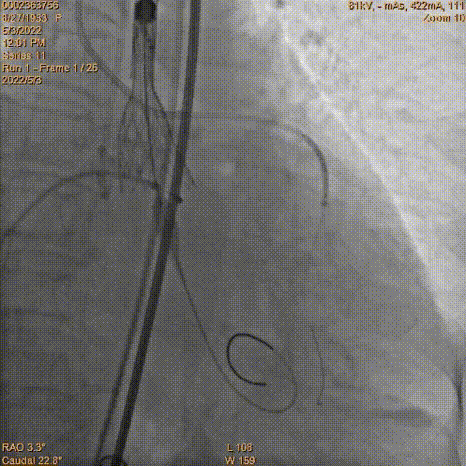

瓣膜定位

工作位造影

工作位冠脉球扩

瓣膜释放2/3同时发现患者血压降低,立即释放冠脉支架

瓣膜脱钩

AV23瓣膜完全释放

术中TaurusElite瓣膜系统优异的输送性能,保障了术中轻松过弓、顺利跨瓣。钟志雄院长团队通力配合、精准释放,充分利用TaurusElite可回收功能,在瓣膜释放至2/3时,多角度评估瓣膜植入深度、锚定力以及冠脉灌注情况。此时患者血压偏低,根部造影评估后,考虑左主干开口受限冠脉灌注不全导致。随即释放预埋支架,行烟囱支架技术保护冠脉。完成冠脉保护后,确认瓣膜植入深度合适、锚定力稳定,故缓慢逐个脱钩,进行瓣膜释放。